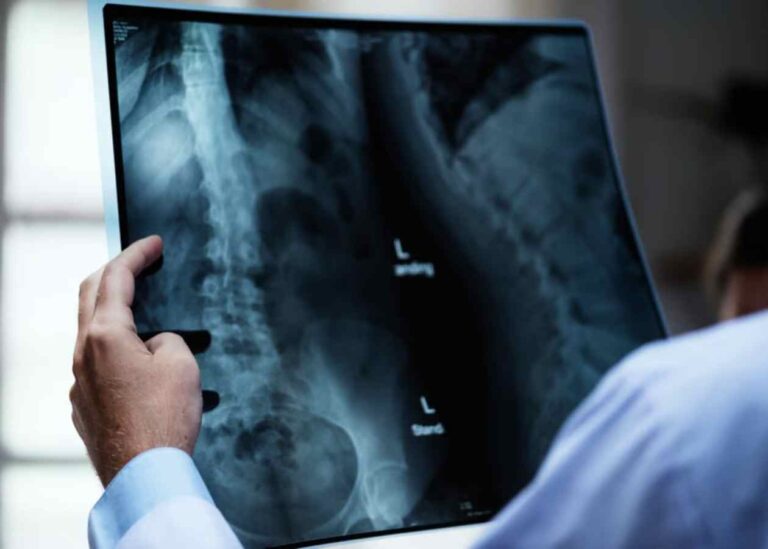

Bel sağlığı, yaşam kalitemizi doğrudan etkileyen en temel unsurların başında gelir. Ancak bazen omurgamızdaki dizilim bozulur…

Yaşam kalitesini ciddi oranda etkileyen, hareket kabiliyetini kısıtlayan ve genellikle yaşlanmaya bağlı olarak gelişen spinal kanal…